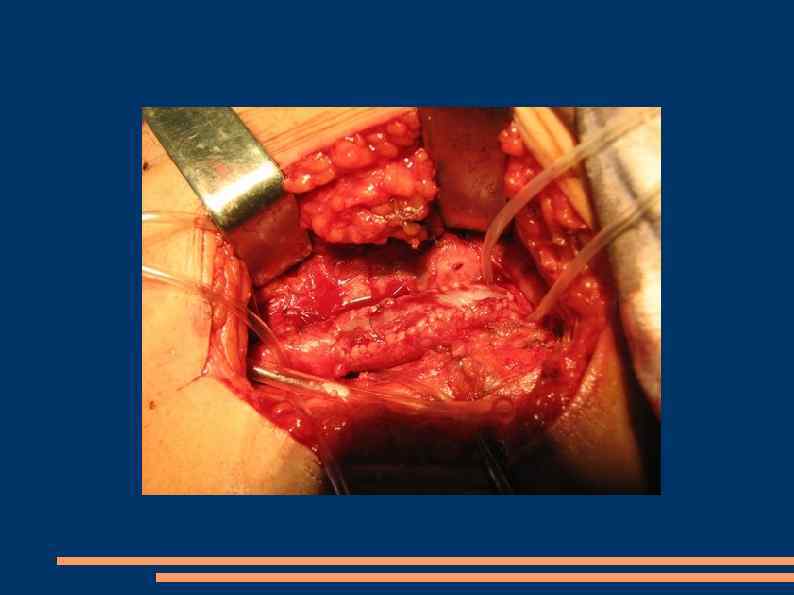

Эндартерэктомия Полуоткрытый способ Закрытый Открытый эверсионный

Открытая эндартерэтомия

Полузакрытая эндартерэктомия

Эверсионная эндартерэктомия